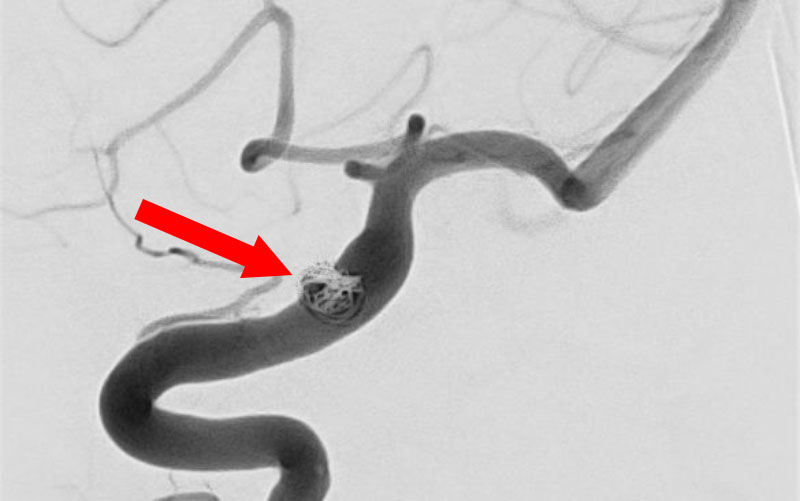

No.1631 手術中